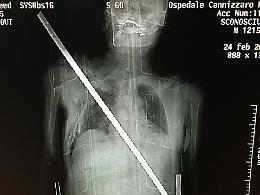

«Io, trafitto da una barra di ferro salvato dagli "angeli" del Cannizzaro»

CATANIA - Si sente un miracolato, dopo essere volato giù dal ...